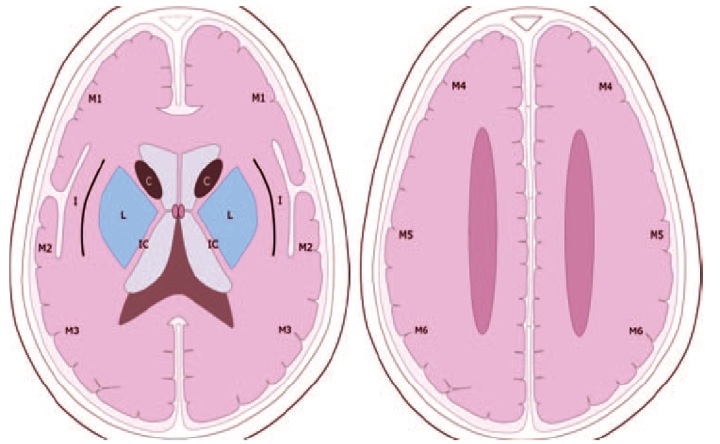

Usamos la escala ASPECTS: The Alberta Stroke Programe Early CT Score.

El Alberta Stroke Programme Early CT Score (ASPECTS) es un sistema estandarizado de interpretación de la TAC cerebral para los ictus isquémicos de la circulación anterior. Interpretación:

- El análisis se realiza sobre dos cortes axiales de la TAC

- El primero a nivel del tálamo y ganglios de la base (plano A).

- El segundo adyacente al borde superior de los ganglios de la base, sin que se visualicen los mismos.(plano B).

- En los dos planos, el territorio de la arteria cerebral media se divide en 10 regiones, valorando cada una en 1 punto.

- M1 : región cortical anterior de la ACM

- M2 : región cortical lateral al ribete insular.

- M3 : región cortical posterior de la ACM

- M4, M5, M6 : región cortical anterior, lateral y posterior de la ACM, aproximadamente 2 cm por encima de M1, M2, M3, respectivamente.( Plano B)

- M7 : Nucleo lenticular

- M8 : Núcleo caudado

- M9 : cápsula interna

- M10: ribete insular

- Se sustrae un punto por cada región donde se aprecia un cambios isquémico précoz (Hipoatenuación o efecto de masa local)

- Una puntuación del ASPECTS inferior o igual a 7 se asocia a una morbimortalidad elevada y mala recuperación funcional.

- Una puntuación ASPECTS de 10 significa que el TAC es normal.

- Una puntuación de 0 implica una afectación difusa de todo el territoio de la ACM

- El riesgo de hemorragia intracerebral siguiendo la terapia trombolíca es mayor si la puntuación es igual o menor de 7.